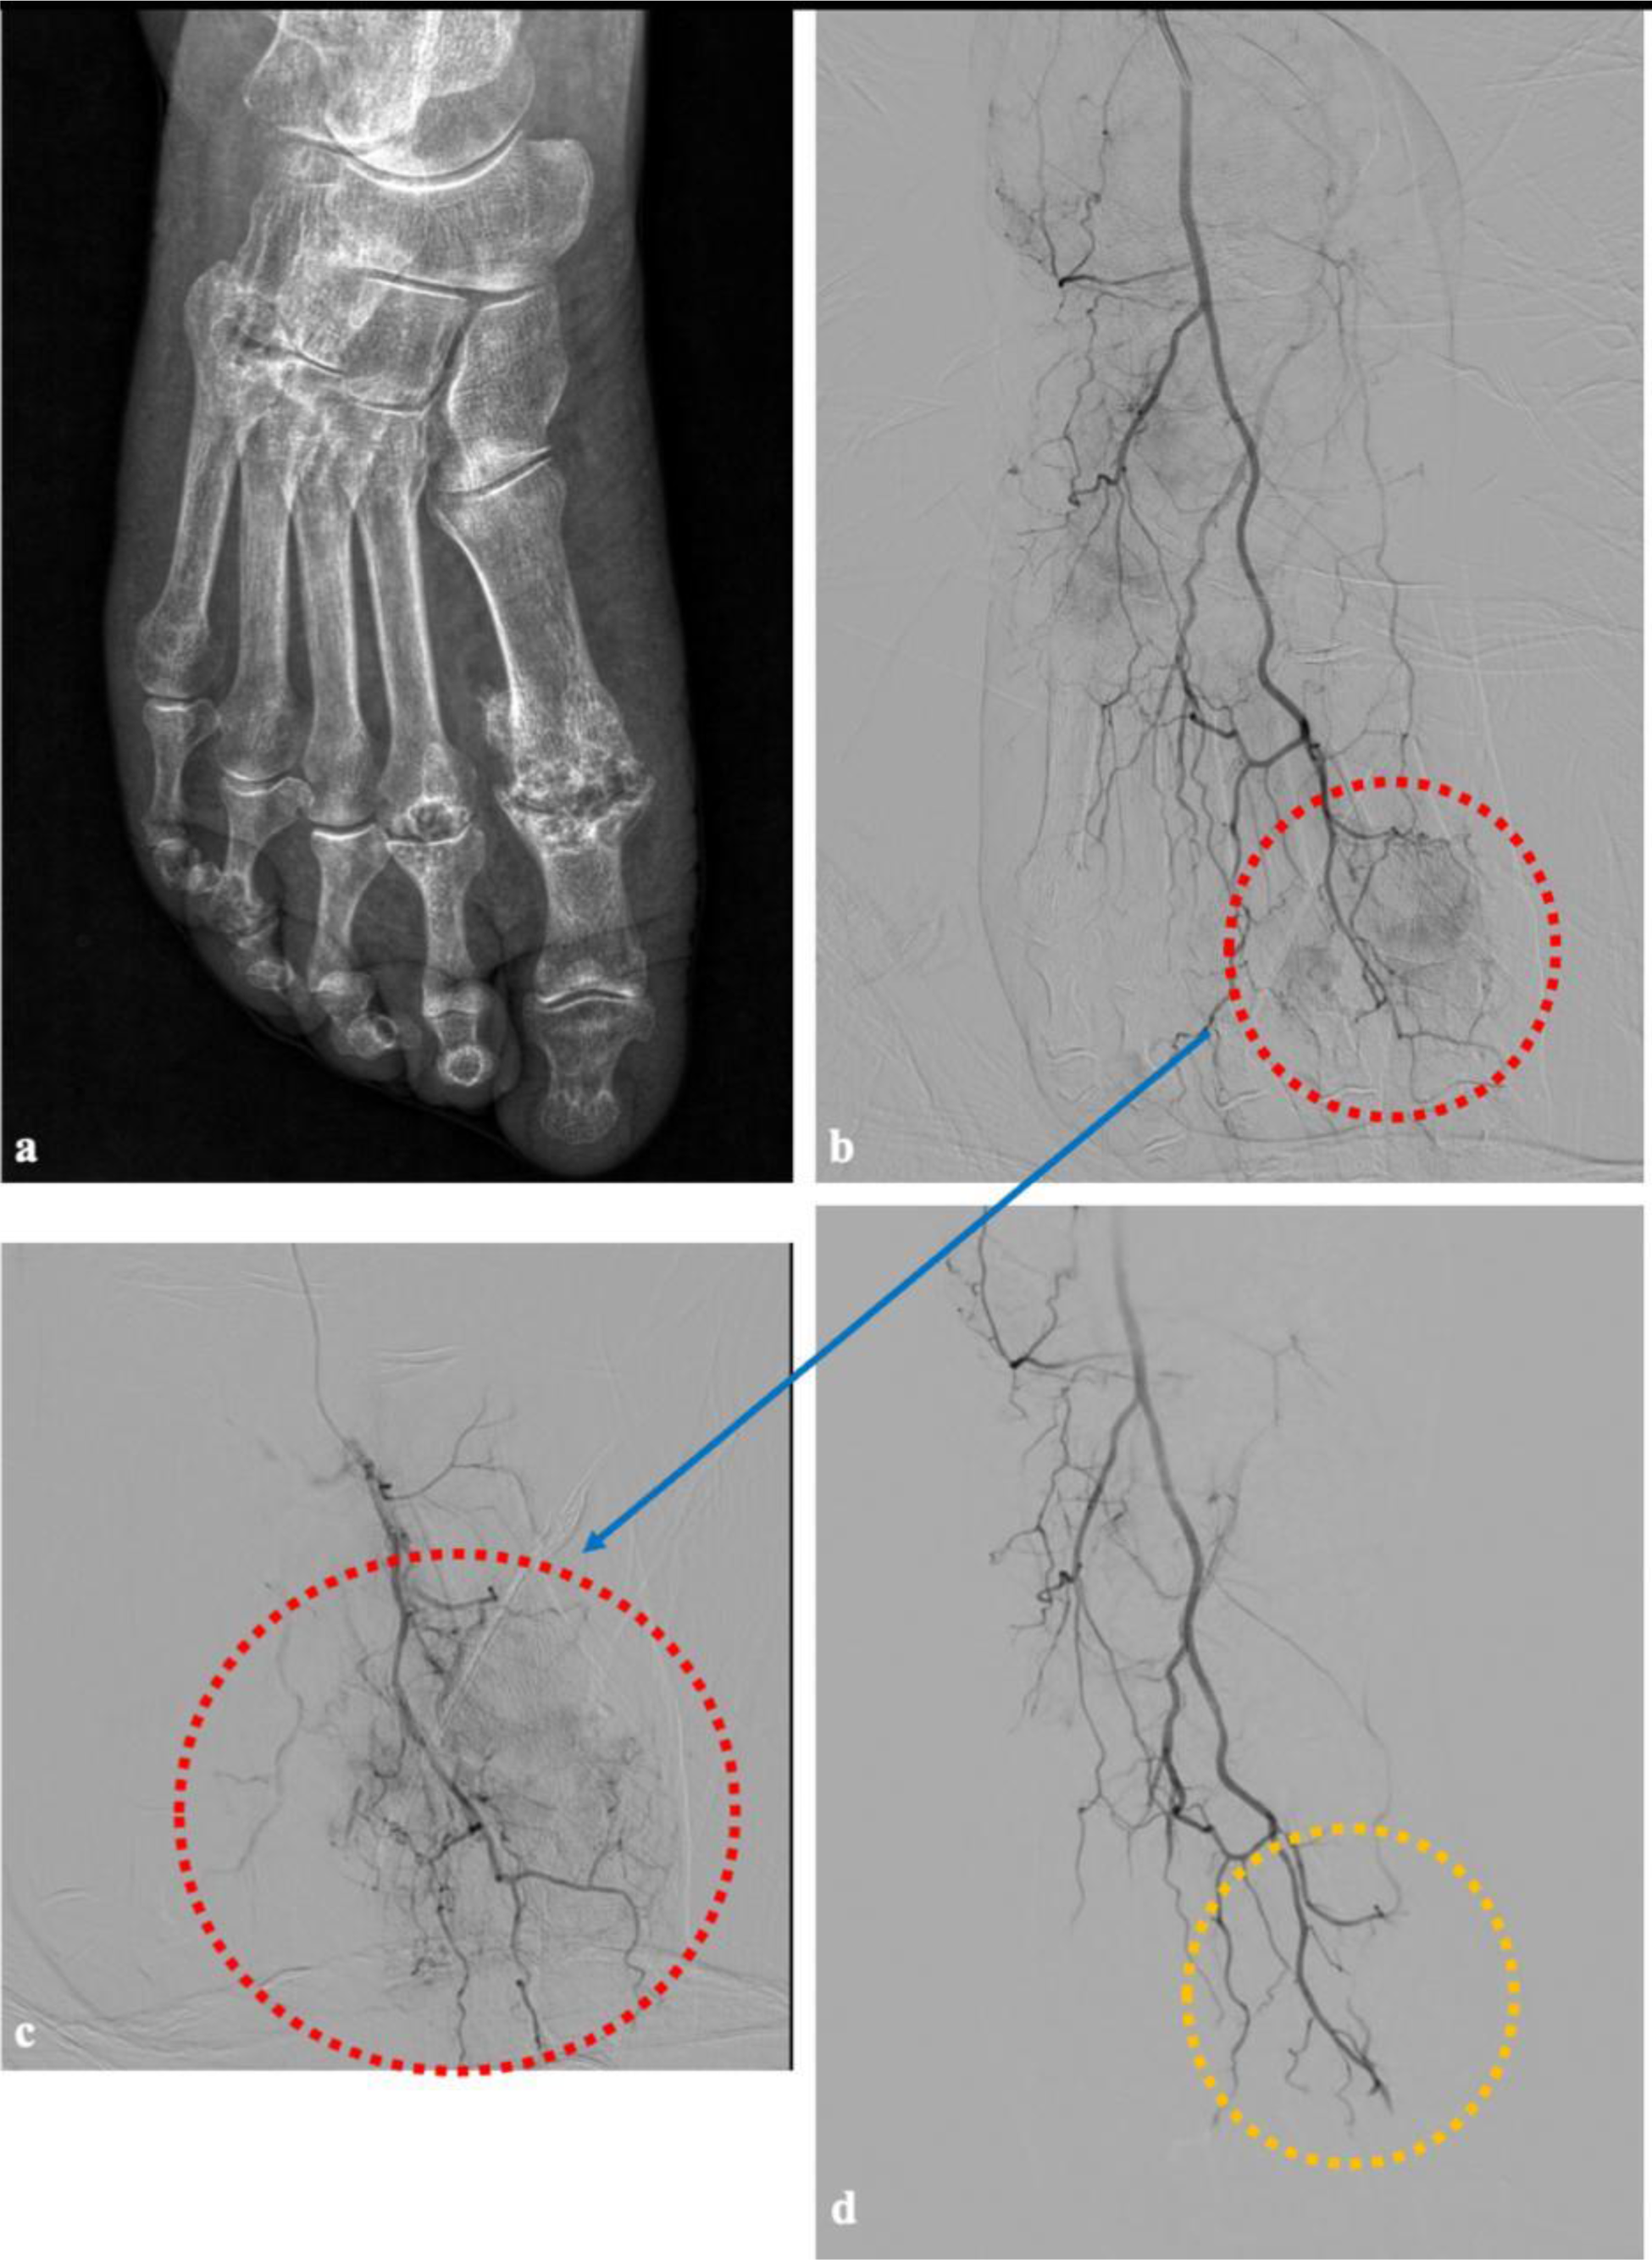

Methods: Patients with chronic MTPJ pain with diverse etiologies were enrolled. Pre-procedural radiographs assessed bony structures, joint space narrowing, and signs of osteoarthritis (Figure 1a and 2a). Following local anesthesia with 2% prilocaine, vascular access was established using the Seldinger technique via the common femoral artery with 4F vascular sheath in antegrade approach. Prior to imaging, patients received 3000 IU of heparin sodium. The procedure began with roadmap imaging using a 0.035-inch hydrophilic soft guidewire and a 4F vertebral catheter to access the anterior tibial artery through the popliteal artery. Angiographic imaging identified hypervascularity in the first MTPJ, and superselective catheterization of the dorsal metatarsophalangeal artery was achieved using a 1.8 F microcatheter and a 0.014-inch guidewire. Embolization was performed using an imipenem/cilastatin suspension, administered in incremental doses of 0.5 mL until hypervascular blush resolved, while preserving distal vascular patency. Steps of the procedure were demonstrated in Figure 1b-c-d and 2b-c-d. Hemostasis was achieved by manual compression of the femoral puncture site for 15 minutes, and patients were observed in the recovery unit for six hours. All patients were discharged on the same day in the absence of complications. Clinical parameters, including Visual Analog Scale (VAS) scores, functional disability, and weekly analgesic use, were documented pre-procedure and at 4 weeks post-procedure.

Preporcedure radiographic and procedural angiographic images of a patient with left foot embolization. In image (a) a plain radiograph image of the patient with underlying gout and narrowing in joint space suggesting osteoarthritis is given. The first procedure image (b) represents a subtracted DSA view of the entire left foot, obtained by injecting contrast through the A. dorsalis pedis. The image (c) is a non-subtracted (mask-less) angiographic view of the same region. In both images, a significant vascular blush is observed at the level of the first metatarsophalangeal joint of the left foot, followed by an enhanced appearance of venous structures due to increased inflammation. After the first dorsal metatarsophalangeal artery was superselectively catheterized using a microcatheter (c), the resulting image demonstrates a more prominent vascular blush and increased visualization of venous structures. Following superselective catheterization and embolization with imipenem/cilastatin, the blush is observed to disappear while preserving the distal vascular structures in image (d).